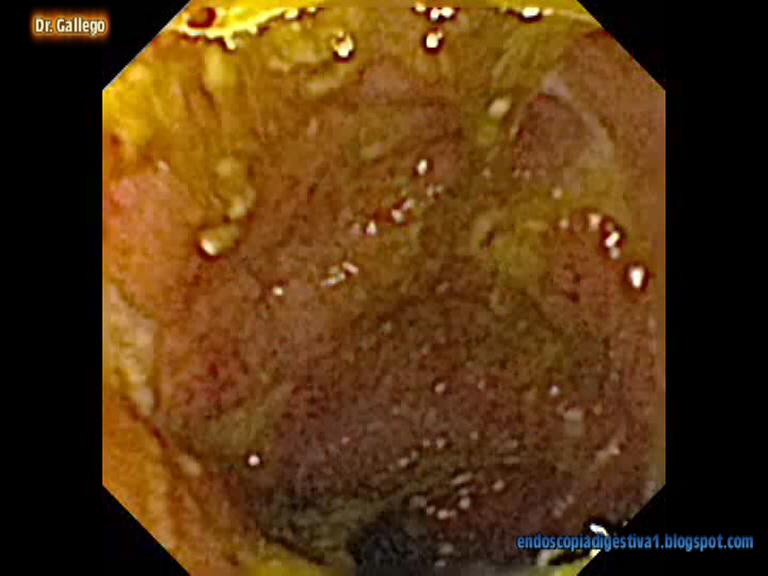

Se decidió realizar un estudio con cápsula endoscópica (Endocápsula OLYMPUS), donde aparecieron lesiones en ileon distal y terminal muy sugerentes de EC (mucosa en empedrado, segmentariedad, estenosis y úlceras serpinginosas con importante edema perilesional).